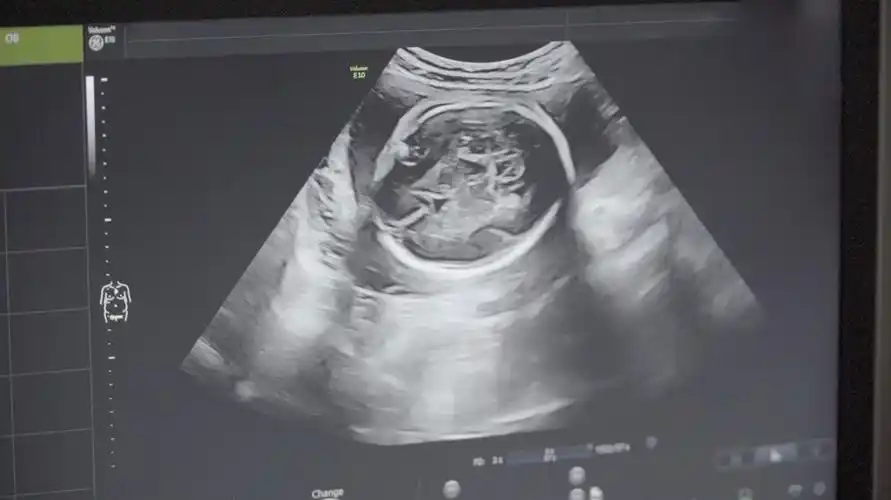

在孕中期开始,进行b超检查的时候,我们会看到b超单上会有双顶径和股骨

b超单上隐藏的秘密,教你一分钟读懂它!

如何看懂产检b超单?宝妈手把手教你_宝宝_胎盘_情况

不妨看b超单上的这3个数据,准确率极高!_宝宝_进行_孕妇